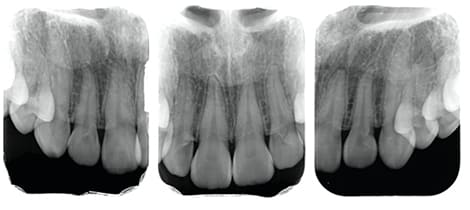

Case01

- 原因

- ガミースマイル

- 治療回数

- 1回

- 治療期間

- 術後治癒も含めて約1か月

- 治療内容

- ガミースマイル改善治療

- 治療費用

- 121,000円

(1ブロックあたり、6前歯部分)

笑った時に歯茎が見えてしまうガミースマイルを改善したいとのことでご来院された患者様です。術後も大変満足していただきました。